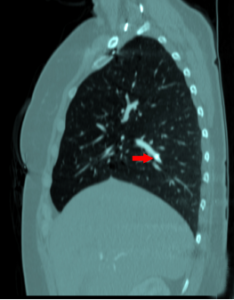

CT sagital bone window;